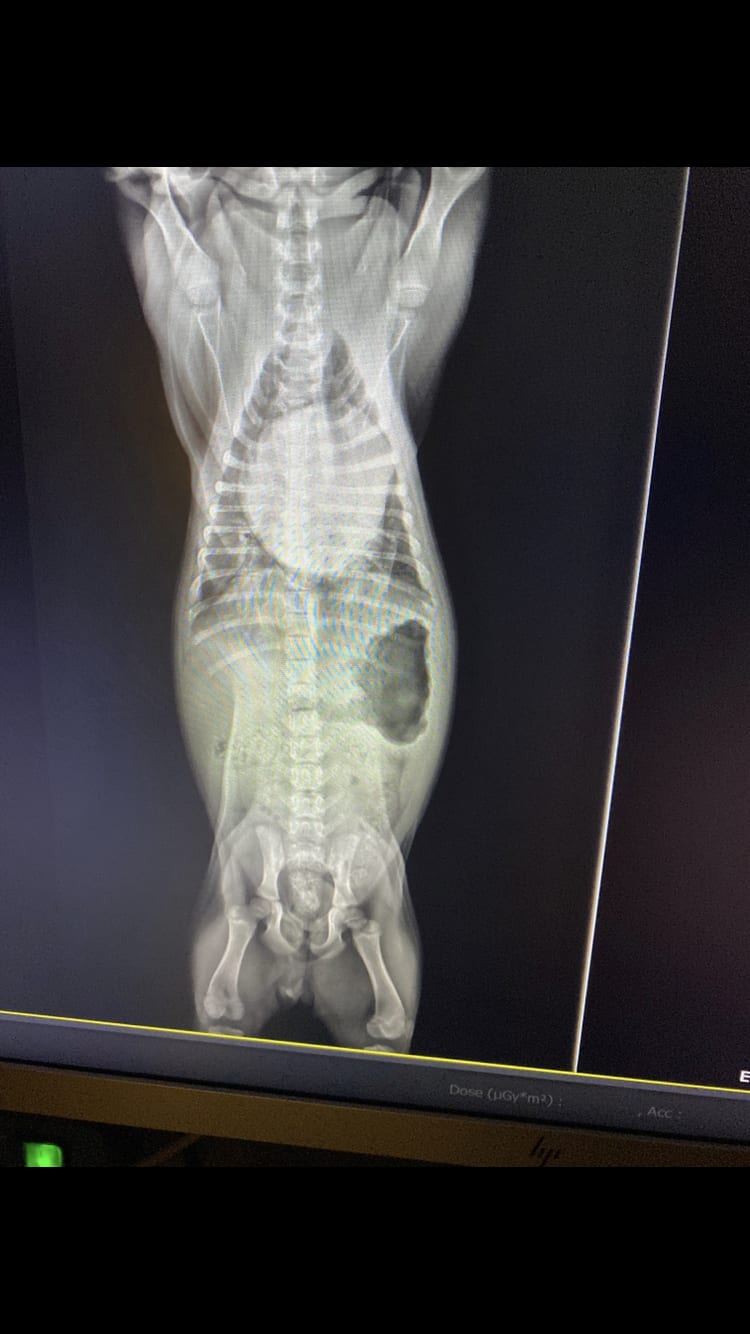

My French Bulldog puppy's X-ray shows enlarged heart. What's wrong?

Pet's info: Dog | French Bulldog | Female | unspayed | 3 months and 1 day old | 7 lbs

This is an X-ray we were given by the vet. What is the diagnosis?

It doesn't work like this i'm afraid, you need to provide medical history and symptoms in order for anyone to check and analyse the x-ray. what i can tell you is that there is an enlarged heart and a lot of air in the stomach.